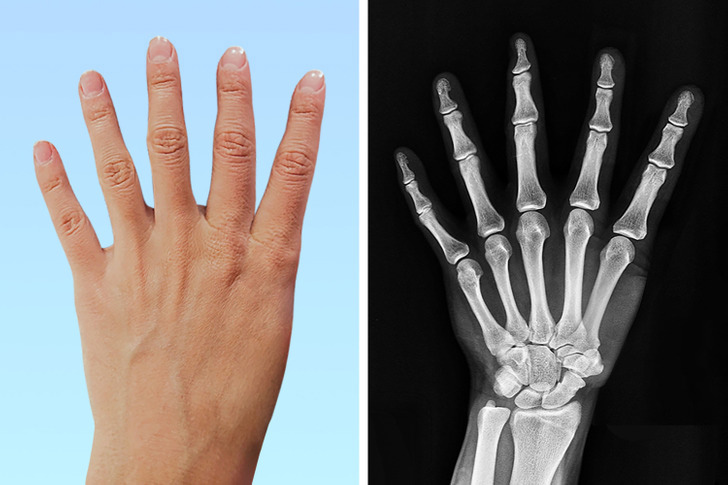

داشتن شست با ۳ بند یا داشتن انگشت ششم

داشتن شست با سه بند یا انگشت ششم، غیرعادی و نادر به نظر می رسد. از هر ۱۰۰۰ نفر فقط ۱ نفر انگشت ششم دارد و از هر ۲۵۰۰۰ نفر ۱ نفر انگشت شست با سه بند دارد. این یک بیماری نیست و داشتن این ویژگی در برخی زمینهها مزایای بزرگی دارد. پزشکان متوجه شدند که مغز این افراد کاملاً میتواند این اندام اضافی را کنترل کند و هیچ تفاوتی با دست های معمولی ندارد.